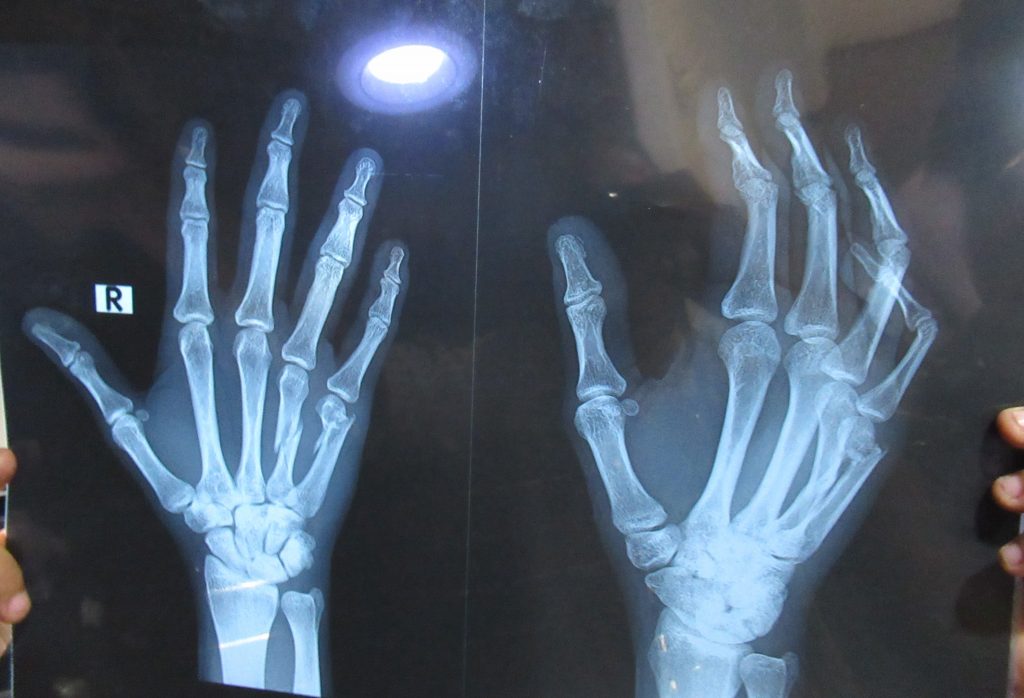

Weak, bleeding, and confused, Adam limped toward the Mak Nimir Bridge, where he had seen the trucks enter. He hid in a tent and wrapped himself in a carpet. A different RSF officer discovered Adam hiding there and ordered two other protesters to help hold him up as he walked to Nile Street. “On the way my phone and keys were taken. I arrived at Nile Street and found a lot of injured people. One person was laying on his stomach in his vomit; I didn’t know if he was dead or alive.” He estimated seeing hundreds of injured detainees at the site, including older women and children, being kept there by RSF soldiers armed with whips and sticks. Adam was physically unable to mount the large truck that had come to transport injured people, so he was placed in an ambulance and taken to Omdurman Military Hospital at around 7 a.m. at the Military Hospital, he received treatment for a large laceration on his forehead and several others on his scalp. His left eye was cleaned and bandaged, but no ophthalmologists were available to attend to the tears in his cornea and retina. His arms were both swollen and X-rays taken several days later at Feda’il Hospital confirmed multiple fractures in his hands.

Clinical examination confirmed that Adam’s visible scars and injuries are consistent with defensive wounds from blunt trauma, highly consistent with beating from sticks, whips, and water hoses. He sustained fractures in his hands, lacerations over his forehead and scalp, and severe trauma to his eye causing vitreous hemorrhage and retinal detachment and resulting in permanent vision loss in the left eye.